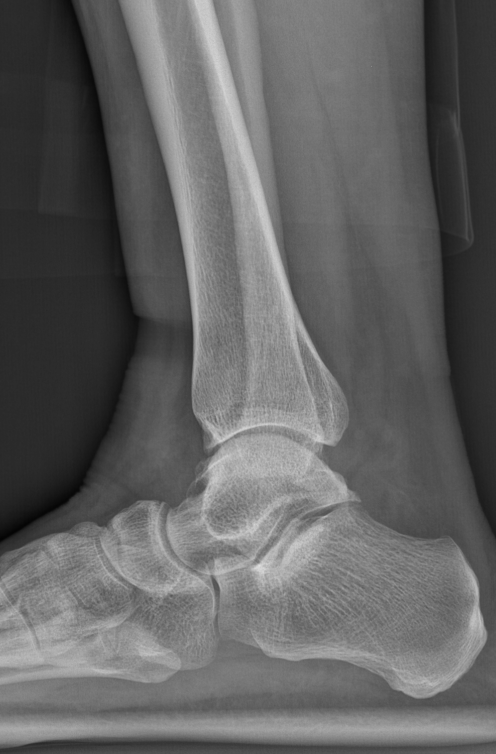

第一台手术的患者是位75岁的叔叔,被“脚脖子”痛缠了4年,疼得越来越厉害,病情已经到了严重阶段。

术前后足力线X线

武勇主任团队给他做了3D打印导板辅助下人工全踝关节置换术。

这种手术适合踝关节病严重的患者,通过替换病变的关节结构,能帮着缓解疼痛、恢复关节活动,让老人日常走路更自在些。